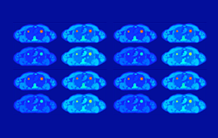

Afin d'en évaluer la fiabilité, les deux équipes ont réalisé très récemment des simulations haute définition, à partir de données médicales TEP-4D actuellement limitées en pratique, et d'un jumeau numérique haute résolution de l'anatomie humaine[2] : les chercheurs ont pu simuler de manière extrêmement réaliste 400 examens TEP dynamiques de thorax, incluant différents tissus (cœur, foie, poumons, tumeurs…), et les traiter avec PET KinetiX. Les résultats sont très encourageants : les cartes paramétriques produites par PET KinetiX reflètent fidèlement les structures biologiques attendues, avec un niveau de détails identique à celui d'images TEP cliniques standards, plus élevé si les données proviennent d'appareils récents à champ de vision étendu.